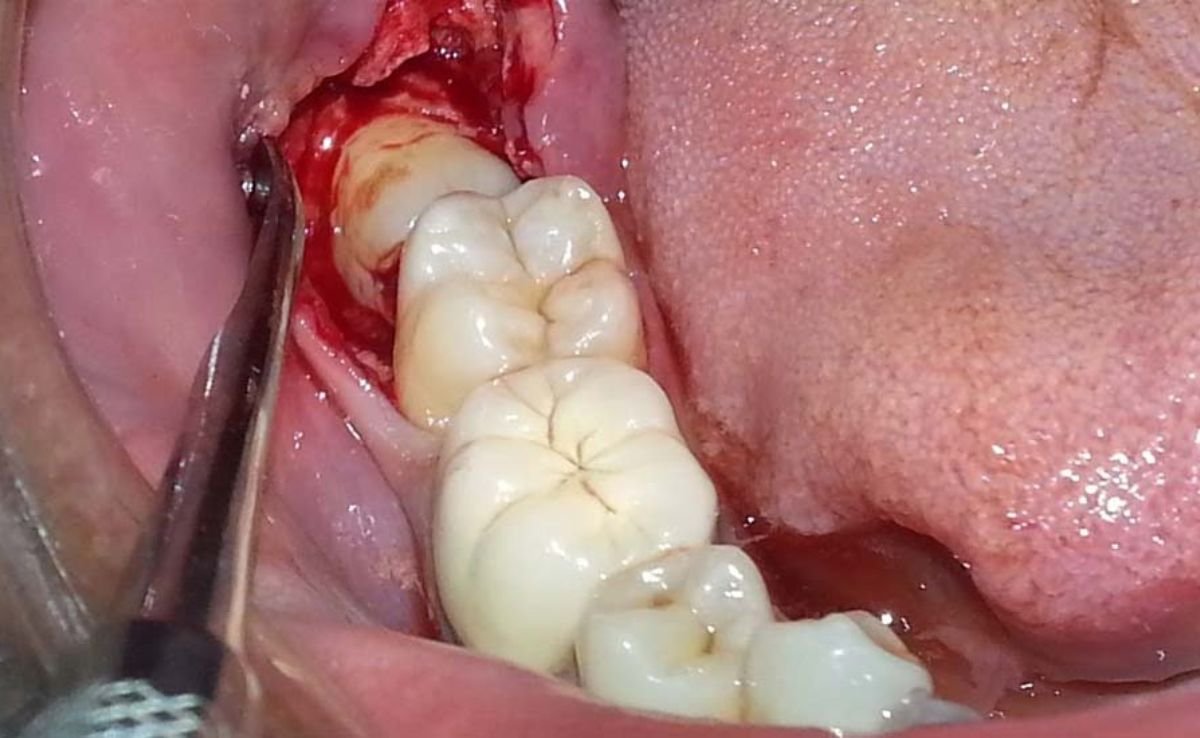

Impacted or partially erupted teeth require surgical extraction. This involves making an incision in the gum, removing some bone if necessary, and carefully extracting the tooth in one or more pieces.

Once the site is fully anesthetized, the surgeon performs a gingival incision to expose the crown and roots. In cases of deeply impacted wisdom teeth, a small portion of the surrounding bone may be removed using a low-speed surgical handpiece with irrigation. The tooth may be sectioned and removed in segments to reduce trauma to the jawbone and adjacent nerves.

The extraction site is then irrigated, disinfected, and sutured using resorbable stitches unless non-resorbable sutures are clinically indicated. We provide every patient with a personalized post-op care pack. Each case is scheduled for a follow-up within 5–7 days for suture review and healing evaluation.